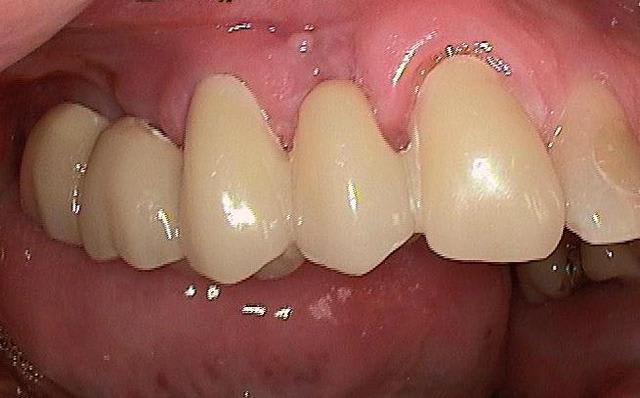

je voulais parler de ce fact pour les implants courts:minimum 4mm os vertical peut suffire (pour eviter un sinus lift externe de tatum) . dans ma pratique depuis quelques années je vois que ca marche , quelques cas cliniques des années passées.

tu as raison , si on est pas sur de soi ou pas expérimenté du tout c est un peu plus risqué... mais c est aussi une bonne alternative je trouve !

bonsoir chicot, merci ( je n ai pas compris le mot baba... :-)) . enfin dans tout les cas la chirurgie reste necessaire, je préfere juste quand cela est possible être moins invasif et proposer au patient une alternative.

Pour ma part même si je préfère le minimal invasif, on ne pourra jamais se passer à 100 % des sinus lift interne.Mais c est tout de même une satisfaction quand cela est possible de proposer une chirurgie moins lourde au patient.